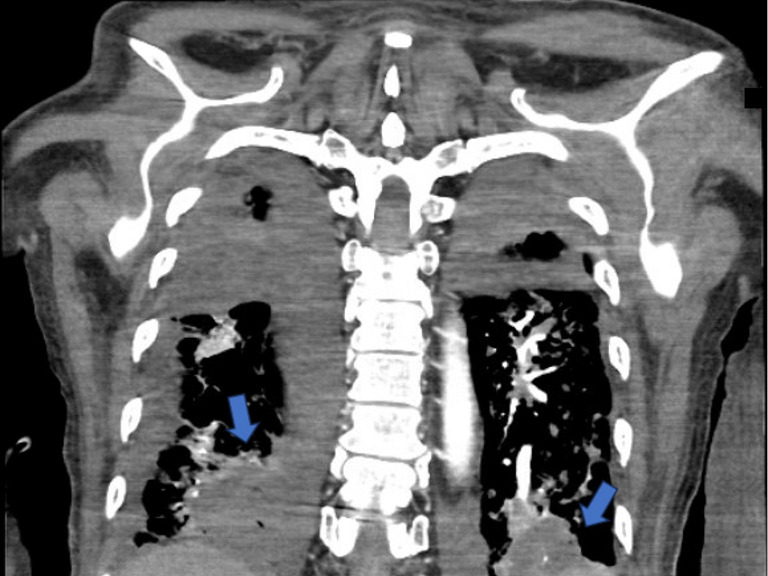

Case description: We present herein the first reported case of peritonitis secondary to jejunal and cecal perforation secondary to angio-IA after lung transplantation (LT) in a 62-year-old male. The patient was admitted to the hospital for acute cellular rejection requiring high-dose immunosuppression. His course was complicated by respiratory failure secondary to IA, with resulting multiorgan system dysfunction during which time peritonitis was noted on examination and cross-sectional imaging demonstrated pneumatosis, portal venous gas, and pneumoperitoneum. The patient required emergent surgical intervention and underwent an exploratory laparotomy, jejunal resection, right hemicolectomy, and end ileostomy with colonic mucus fistula. Final pathologic analysis of resected specimens demonstrated angio-IA in both the jejunal and cecal segments with associated transmural ischemic necrosis.